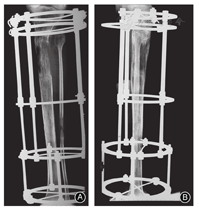

1)成骨不良

成骨不良是指延长过程中新骨的数量和质量不足(图4)。X线表现为低密度骨痂,此时应减慢延长速度,查找原因;鼓励患者辅助下负重,严密观察;必要时可在麻醉下行细克氏针局部刺激。低密度骨痂不连续时应停止延长或适当回缩,1~2周后再慢速延长,观察2周后经X线确认有连续性新骨后再确定延长速度。有学者报告采用定量评价监测骨形成[24]、并辅以低强度超声[25]、BMPs应用[26]等促进延长区成骨。

腓骨提前愈合主要是胫骨延长手术操作不规范、术后管理不到位所致。腓骨头穿针贯穿胫骨是小腿延长手术的重要操作步骤,若腓骨头中点不能与胫骨穿针牢固固定,胫骨延长到一定数量必然发生为腓骨头被牵拉下移(图4)。Kim等[28]常用切开穿针以确保进针的位置,小儿或骨质疏松者通常在腓骨近端再增加1枚螺纹半针。腓骨头下移<3 cm者无临床症状,很少影响膝关节功能。如果胫腓骨远端未同时穿针固定,随着胫骨的延长可引起外踝上移和踝外翻畸形,只要规范穿针操作此并发症完全可以避免。

3)力线偏移

肢体延长过程中截骨远端相对近端的力线偏移主要表现:①平移畸形,随着延长幅度的增加而逐渐增大。②成角畸形(图4),如果钢针在倾斜张力下强行与外固定器连接,在延长过程中随着张力释放骨段会发生移位;牵拉过程中外固定器不稳定或局部固定失效亦可致骨段移位。③扭转畸形,常见于大幅度延长的病例,表现为"内八字"、"外八字"以及步态异常。这些畸形发生的主要原因是手术截骨安装延长器时,个体化穿针布局欠妥或延长过程中钢针松动所致。成角等畸形可增加附件借助外固定器推拉进行矫正,而扭转畸形可在延长结束后一次性矫正。